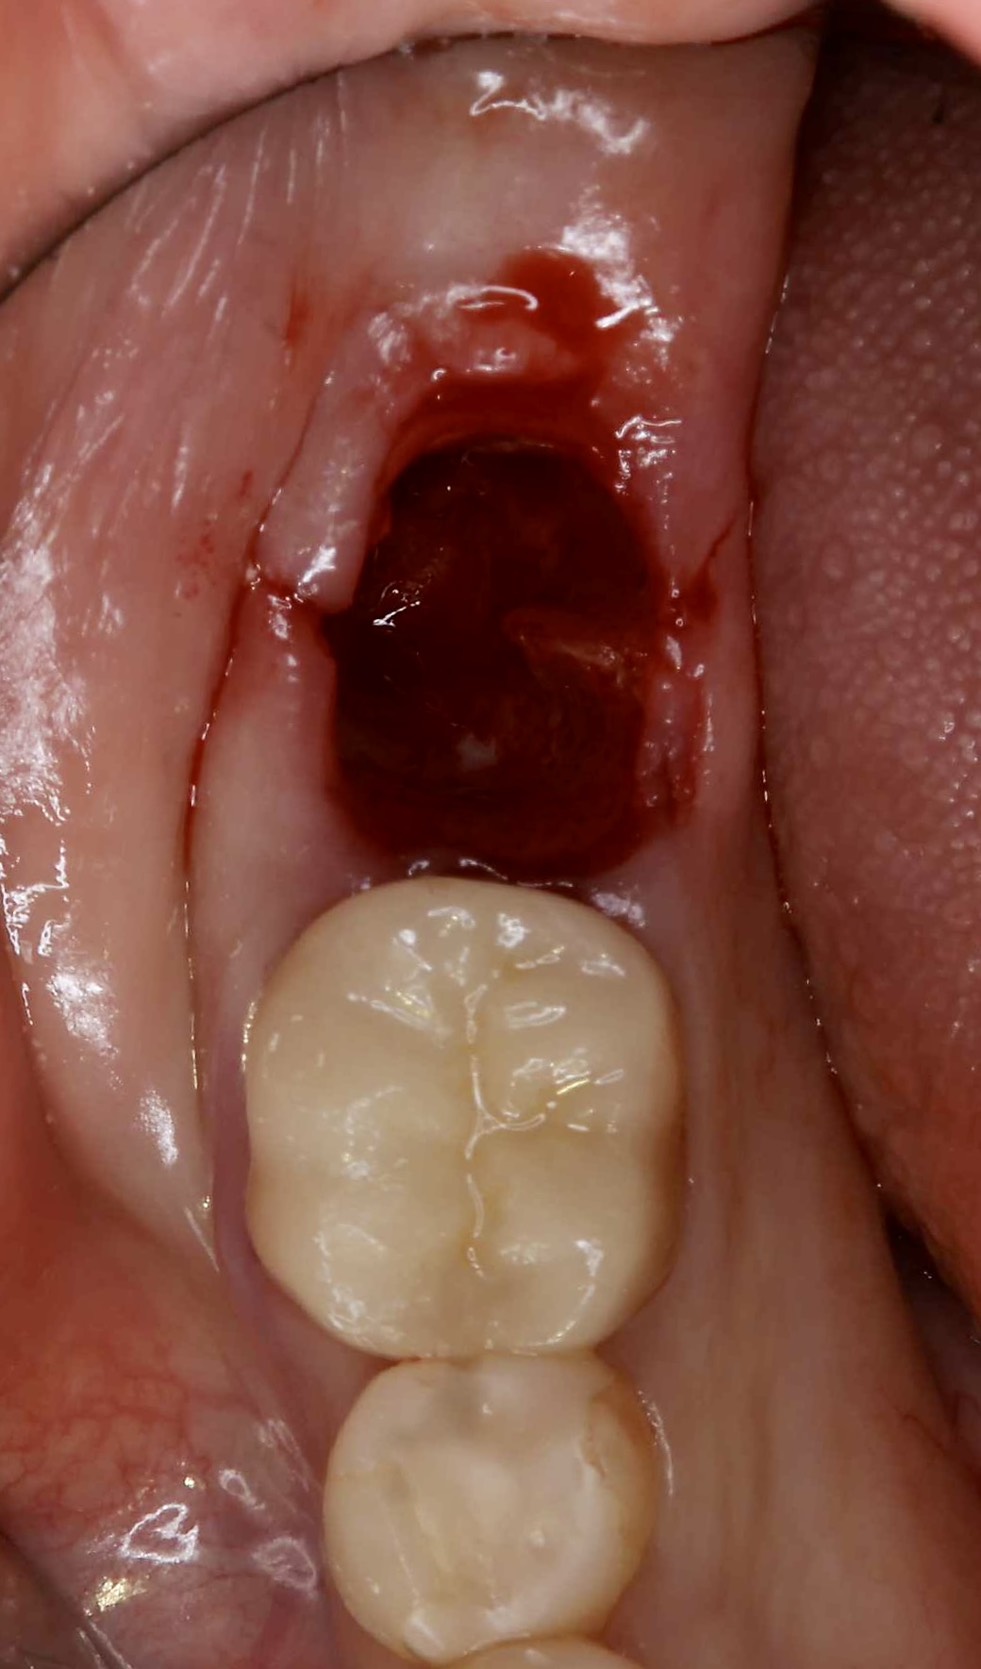

30代、女性、右下に違和感があることを健診中に申され、インプラント治療を行いました。

| 診断結果 | 右下7番歯根破折 |

| 治療内容 | 抜歯即時インプラント |